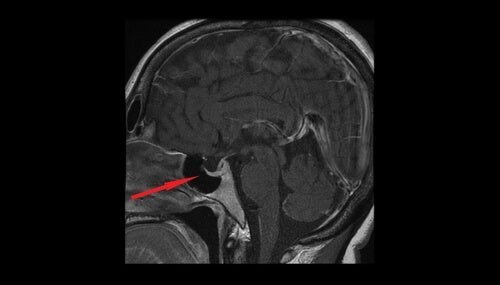

Os baixos níveis de hormônio antidiurético farão com que os rins excretem muita água. O volume de urina aumentará, o que causará desidratação, e uma diminuição da pressão arterial. Além disso, os baixos níveis de hormônio antidiurético podem indicar danos no hipotálamo ou na hipófise, bem como polidipsia primária.